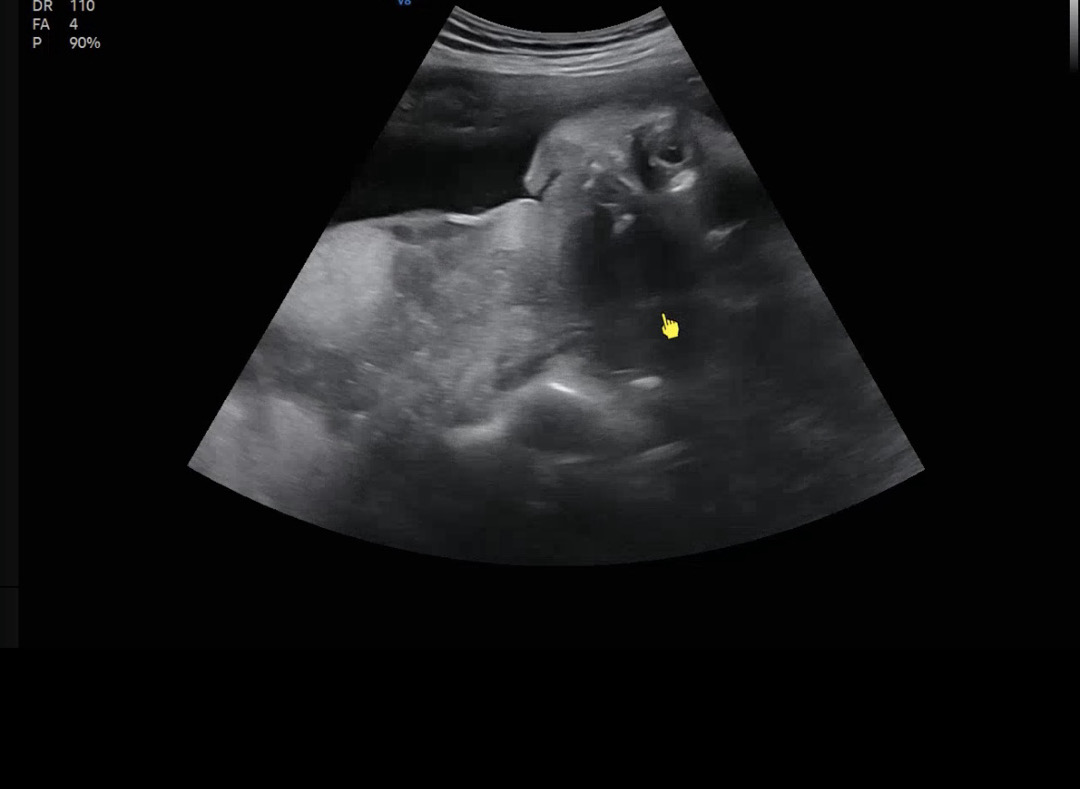

오른쪽 상단 동그라미 쉽게말하면 안구? 눈동자? 에용 눈꺼풀쪽은 안보여서 뜬건지안뜬건지는 모르겠네용 눈감아도 초음파가 피부약간 안쪽을 스캔하는 각도면 눈동자를 볼수있어요

맘들아 촘파 사진 잘보는 분들 좀 봐줘 이거 눈뜬거얌?

눈 뜬것 같이 보이는데 맞나,,?

초음파 중에 눈을 잠시 뜰수 있다고는 하긴 하는데.. 이번에 초음파 보러 가니까 저도 저렇게 보여서 저게 눈뜬걸까요. 물으니 그게 아니라 걷어내고 찍어서 그렇다고 하셨어요. ㅎㅎ